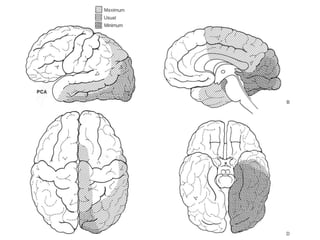

Distribuição cortical

• A ACM irriga toda convexidade cerebral, exceto pólo

occipital, frontal nem a margem superior do hemisférios.

• A região cortical é dividida em 12 áreas de irrigação.